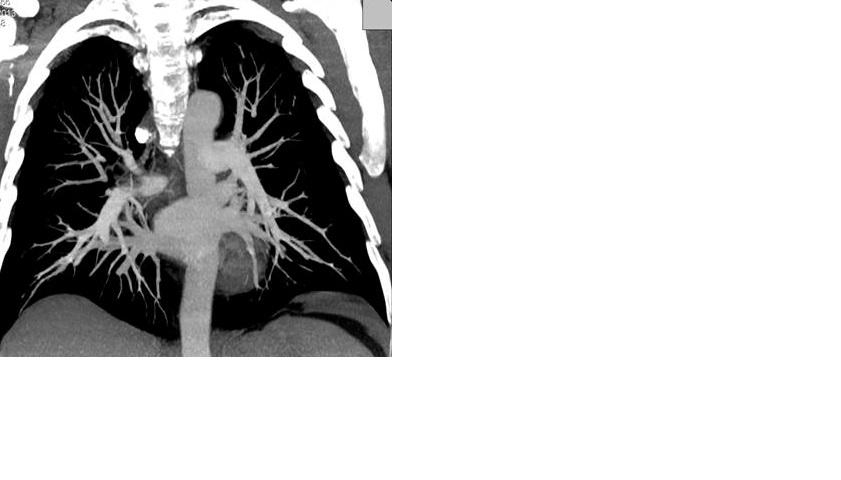

Для окончательной верификации диагноза (так как состояние пациента оставалось гемодинамически стабильным) была проведена мультиспиральная компьютерная томография (мсКТ), которая подтвердила наличие ТЭЛА и выявила множественные тромбы в основных ветвях обеих легочных артерий (ри.3. МсКТ при поступлении).

Рис. 3. Данные мсКТ с контрастированием сосудов малого круга кровообращения (исходно и после проведения тромболитической терапии).

МсКТ при поступлении (13.02.13) МсКТ после проведения ТЛТ (18.02.13)

Б. Множественные тромбы в основных ветвях легочных артерий![]() |

Б. Единичные тромбы в субсегментарных ветвях легочных артерий![]() |

Учитывая клиническую картину заболевания (нормальные параметры центральной гемодинамики), данные инструментальных (признаки дисфункции ПЖ) и лабораторных (повышение уровня тропонина) методов исследования данная ТЭЛА была классифицирована как субмассивная или промежуточного риска [1,7]. В то же время, наличие одышечного (SpO2 – 87%) и болевого синдромов, массивность тромботической закупорки основных ветвей легочной артерии, выраженная степень дисфункции ПЖ, а также отсутствие видимых факторов риска развития кровотечений явились основанием для проведения тромболитической терапии (ТЛТ). ТЛТ проводилась альтеплазой в дозе 100 мг в течение 2-х часов. Во время проведения ТЛТ отмечалась кровоточивость десен, которую удалось остановить полосканием полости рта раствором аминокапроновой кислоты. Других кровотечений не было. Через 12 часов после окончания ТЛТ состояние пациента существенно улучшилось, боли в грудной клетке и одышка прекратились. Насыщение артериальной крови кислородом при пульсоксиметрии (SpO2) возросло до 96% (дыхание воздухом), ЧСС снизилась до 70 ударов в минуту. Повторная эхоКГ выявила существенное уменьшение размеров и пергрузки ПЖ, снижение степени легочной гипертензии (рис.2. Эхо КГ после проведения ТЛТ). Контрольная мультиспиральная КТ, проведенная на 5-е сутки после ТЛТ (рис.3.), выявила значительное улучшение легочного кровотока, с наличием единичных тромбов в субсегментарных ветвях легочной артерии. При компрессионной сонографии вен нижних конечностей тромбы в глубоких венах нижних конечностей не выявлены (признаки посттромбофлебитической болезни). Пациент был переведен на длительный прием пероральных антикоагуллянтов и выписан в удовлетворительном состоянии. ЭКГ при выписке представлено на рис. 4.